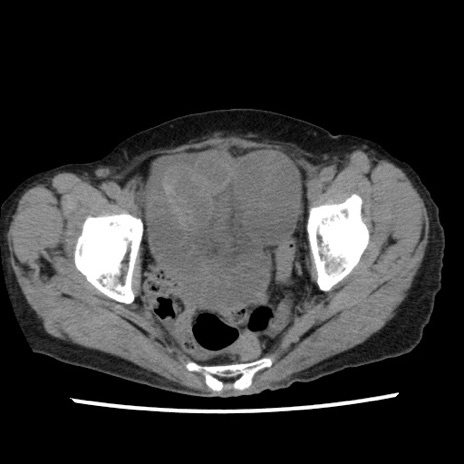

症例1(横断像)

【症例】80歳代女性

【主訴】腹痛

【現病歴】8時間前から腹痛あり来院。

【既往歴】糖尿病、脂質異常症、子宮体癌にて子宮全摘術

【身体所見】意識清明・会話良好だが腹痛で苦悶様、全腹部にわたって反跳痛と圧痛あり

【データ】WBC 13600、CRP 0.14、LDH 224、CK 90